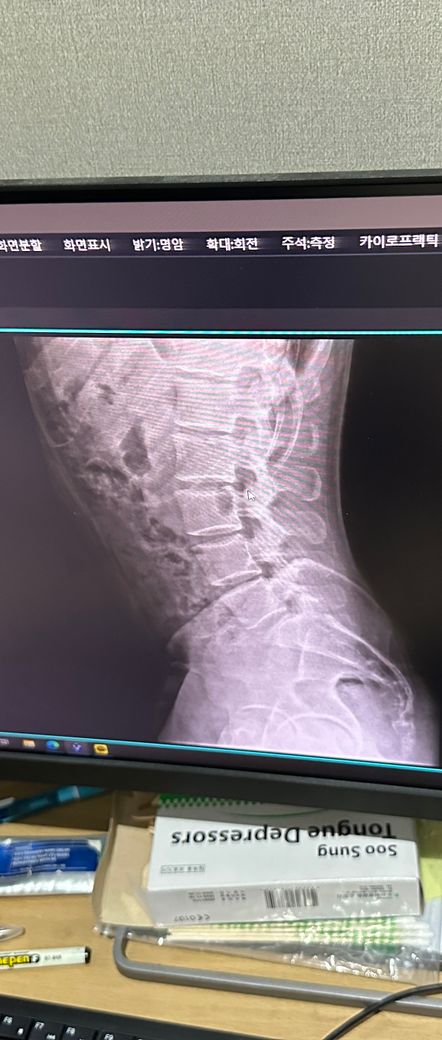

사진은 증상 생기기 일주일정도 전에 정형외과에서 찍은 사진입니다

• 3번 째 사진

엑스레이 사진을 다각도로 봐야겠지만 이 사진으로만 보기에는 흉추측만증이 있으신것 같네요 그로인해 옆구리 통증이 올수 있습니다